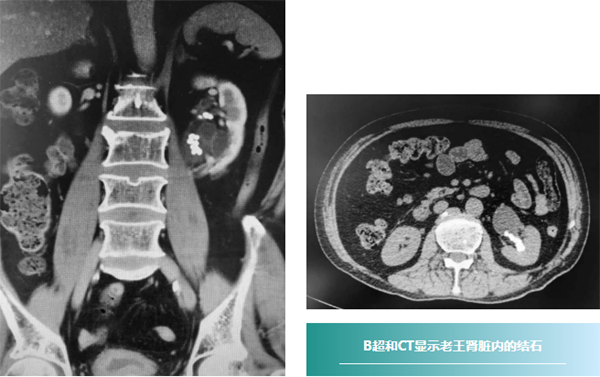

69岁的老王(化名),间断左侧腰痛2年,起初疼痛每2-3个月出现一次,每次使用止痛药都能缓解。最近腰痛发作的频率越来越高,疼痛程度也越来越重。就诊于当地医院,给予保守治疗效果欠佳。B超和CT检查发现其肾脏内几十个大小不等结石,最大者直径约1cm。经皮肾镜碎石术是最合适老王的治疗方式,但是他吸烟50年,患有严重慢性阻塞性肺疾病,长期的肺疾病导致心功能也很差,不能耐受长时间平卧,当地医院评估之后认为麻醉风险过高,建议手术暂缓。